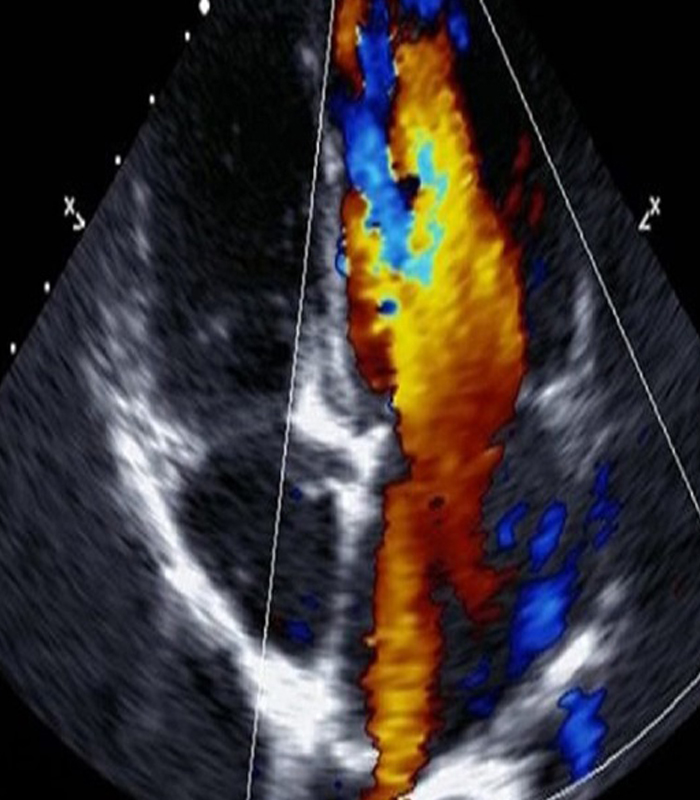

Echocardiography

Critical care echocardiography (CCE) use is rapidly growing and echocardiography is recommended as first-line approach to patients presenting with shock. In most cases the prompt use of CCE offers the opportunity to quickly identify the shock aetiology, with the advantage of being a non-invasive point-of-care tool. Septic shock is among the most common diagnoses of hypotension both in the emergency department and in the intensive care unit. CCE may have a substantial role in sepsis.